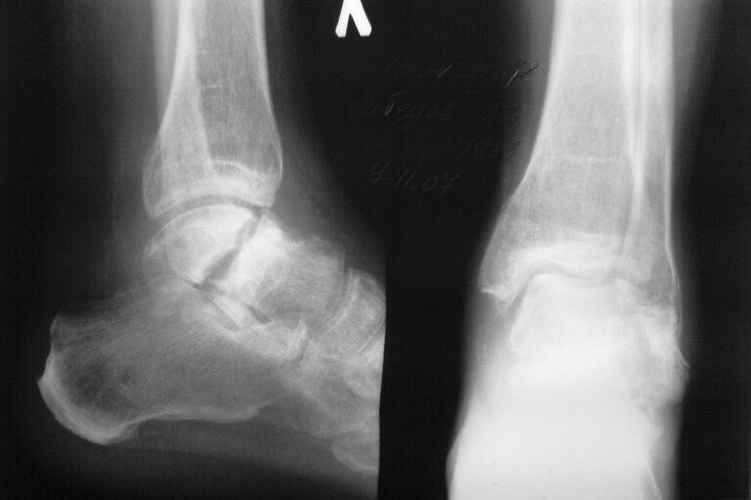

Несросшийся таран

Поступил мужчина 55 лет с диагнозом несросшийся перелом таранной кости через 7 месяцев после травмы.

Беспокоят боли при ходьбе.Тракторист по профессии. От артродеза отказался. Есть другие варианты? Рентген снимок прилагаю.